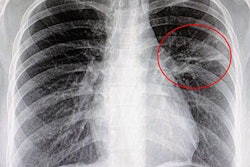

Don't underestimate chest x-rays as a useful technique for illuminating thoracic aorta pathologies, particularly when it comes to highlighting incidental findings, according to Italian research presented at last week's European Society of Cardiovascular Radiology (ESCR) congress in Milan.

Enlargement detection differed significantly statistically between chest x-ray and CTA, whereas thoracic aortic calcification detection did not. The Kappa statistic showed acceptable agreement for TAC detection and virtually nonexistent agreement for enlargement detection. Specificity was high in both evaluations, and this could be explained by considering that when those radiological findings are evident in the chest x-ray, it might be because of their relatively relevant size, according to Mereu and colleagues.

The study results show chest x-rays performed well compared with CTA in the detection of thoracic aortic calcification, and although it performed poorly in the detection of its enlargement, it demonstrated high specificity in both clinical situations.

"Calcification often is evident in a CXR because of its radiopacity, even if the extension is not very large; on the other hand, 3D aorta enlargement has to be pictured on a 2D image, which makes its detection somewhat harder, especially when its enlargement is relatively small in size," they concluded.